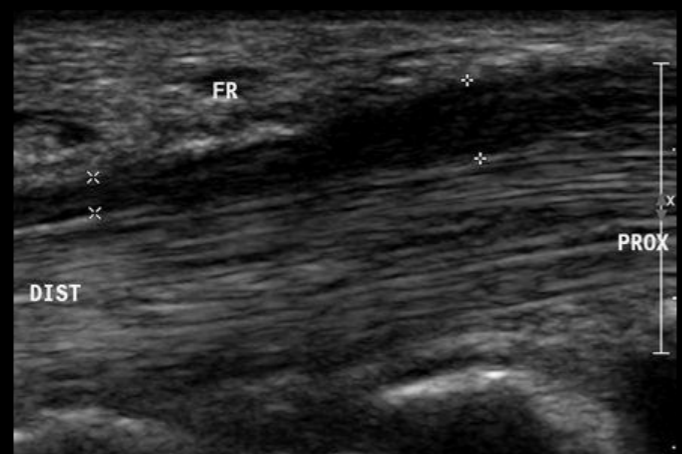

RM tenosinovitis

Hiperintensidad en T2